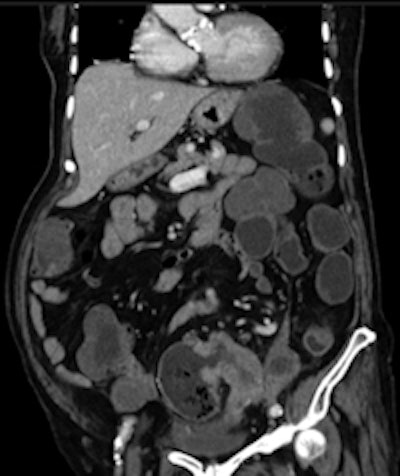

Left: Elderly patient presenting with low-grade bowel obstruction. Optical colonoscopy was denied due to patient's condition, and a CT with water enema was performed in order to detect a large lesion. This was the case because the patient had an almost occlusive cancer of the sigmoid. Right: Crohn's disease involving the transverse colon, with wall thickening and hyperhemia of the colonic vessels. All images courtesy of Dr. Yves Menu.The modalities appear to be becoming increasingly complementary. Follow-up programs can also include VC in association with OC. In patients requiring prolonged follow-up, both methods can be interleaved for the detection of polyps or recurrence.